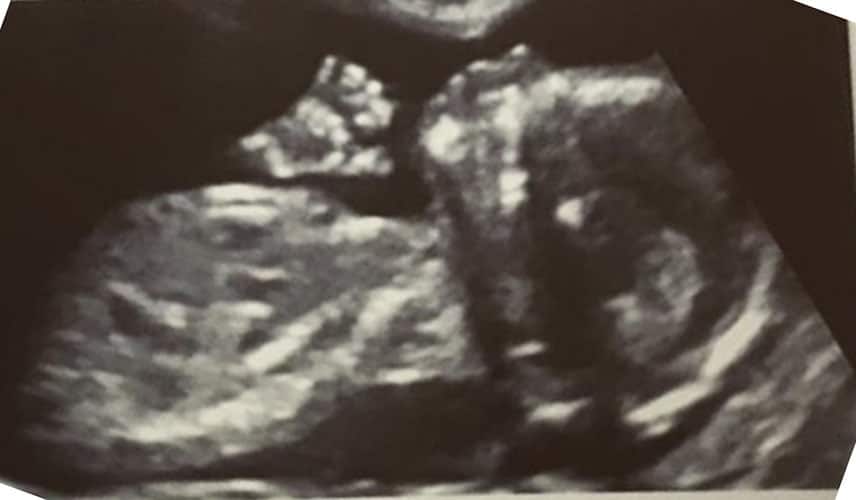

Ultraschallbilder aus dem 2. Trimester (13. bis 28. SSW)

Im 2. Trimester bekommt man oft die schönsten „Ganz-Körper“ Ultraschallbilder. Das Baby ist nun so groß, dass man alles gut erkennen kann und noch nicht zu groß, so dass es noch ganz auf das Bild passt. In dieser Zeit lässt sich meist das Geschlecht bestimmen, wobei manche Babys es einfach nicht preis geben wollen und sich immer so drehen, dass man nichts erkennen kann.